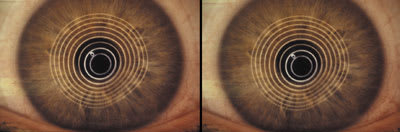

| Figure 3. New reverse geometry SCLs OU. | Figure 4. Photokeratoscopy OD: without SCL (left) with SCL (right). |

Figure 5. Photokeratoscopy OS: without SCL (left) with SCL (right).  |